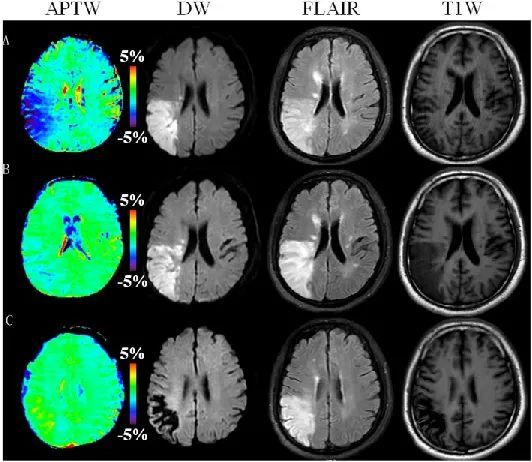

由于APTw MRI 可以敏感提供有关蛋白质含量和pH相关信息,可用于同时发现中风早期缺血期间的 pH 变化和出血期间渗漏到组织中的血液。急性缺血性卒中患者中最终梗死组织和仍然存活组织的APTw值存在显著差异。APTw还可用于判断卒中的时间分期(超急性、急性、早期亚急性和晚期亚急性期)。APTw信号强度与临床卒中严重程度[如美国国立卫生院卒中量表(NIH Stroke Scale,NIHSS)评分]之间呈显著负相关。当临床症状逐渐改善,缺血病变中的APTw信号强度也逐渐增加(图3)。

图3为缺血性卒中患者(男性,52 岁)在发病后1天(A)、6天(B)和34天(C)的图像(或治疗前,治疗后5天/33天)的APTw、弥散加权成像(diffusion weighted imaging,DWI)、磁共振成像液体衰减反转序列(fluid attenuated inversion recovery,FLAIR)和T1-加权图像。APTw图示相应病变区域的信号强度值逐渐增加。发病后1/6/34天的NIHSS评分为6/3/2。(YuL,etal.Front Neurol,2019)